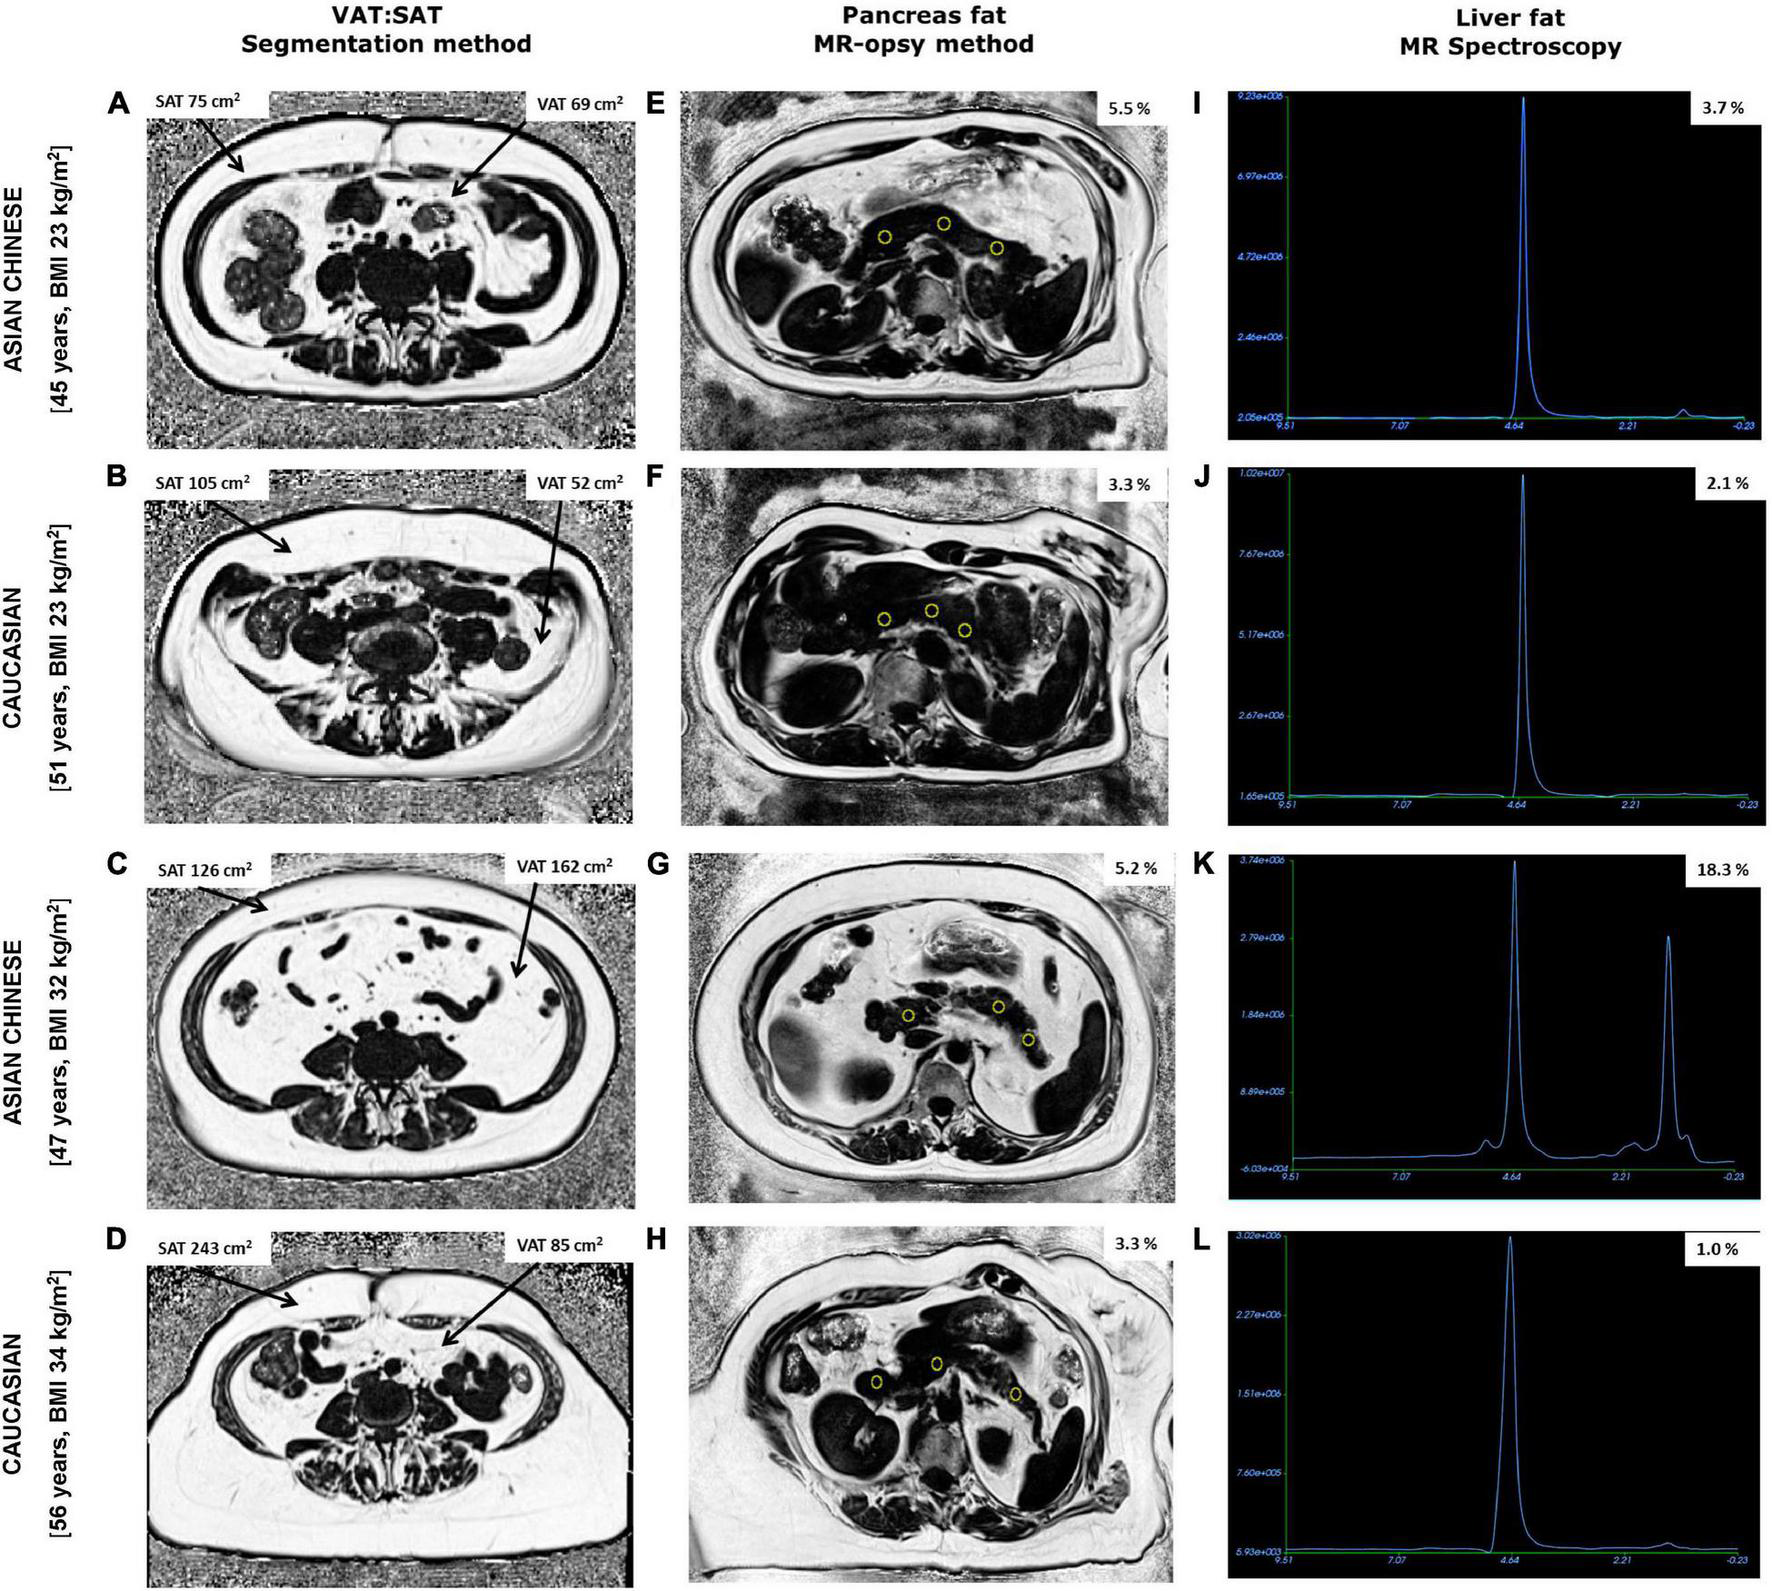

Figure 2. Fat fraction maps obtained from abdominal MRI scans showing subcutaneous (SAT), visceral adipose tissue (VAT), and pancreas fat along with MR spectroscopy of liver fat from two Chinese and two Caucasian women. Chinese women aged 45 years, BMI 23 kg/m2 (A,E,I) and 47 years, BMI 32 kg/m2 (C,G,K) had lower SAT and higher pancreas fat compared to older BMI matched Caucasian women aged 51 years, BMI 23 kg/m2 (B,F,J) and 56 years, BMI 34 kg/m2 (D,H,L), respectively. Notably, VAT, % pancreas and % liver fat were higher in both Chinese women compared with BMI matched Caucasian counterparts exhibiting the TOFI profile.

Mean DXA-% TBF was 39.8 ± 7.6% in the full cohort of women. In accordance with lower bodyweight and stature, DXA-assessed TBF mass (kg) was also significantly lower in Chinese (P = 0.02) but when normalised as % of total soft tissue mass there were no ethnic-specific differences in DXA-% TBF between the Chinese and Caucasian women (Table 1). While MR-assessed SAT (cm2) and MR-VAT (cm2) were again both numerically lower in these smaller stature Chinese women, notably this difference was highly significant for MR-SAT (P = 0.001, Figure 1) but not for MR-VAT (P > 0.05) which was not significantly different from the Caucasian subcohort. In turn, while mean MR-AAT (cm2) was again significantly lower (P = 0.004) in smaller stature Chinese than Caucasian women, there was greater contribution of VAT (34 vs. 28%) than SAT (66 vs. 72%) to the abdominal fat compartment in the Chinese subcohort (Figure 2).